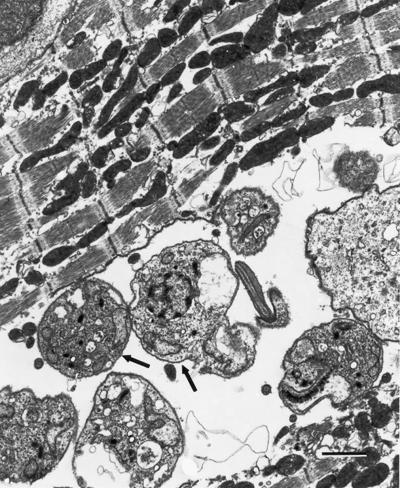

Related Image for Press Use: https://www.plos.org/wp-content/uploads/2013/05/Pathogens_Garg_MAY_7_IMG.tif Caption: T. cruzi (some marked by arrows) in the heart. Credit: Nisha J. Garg, CC-BY